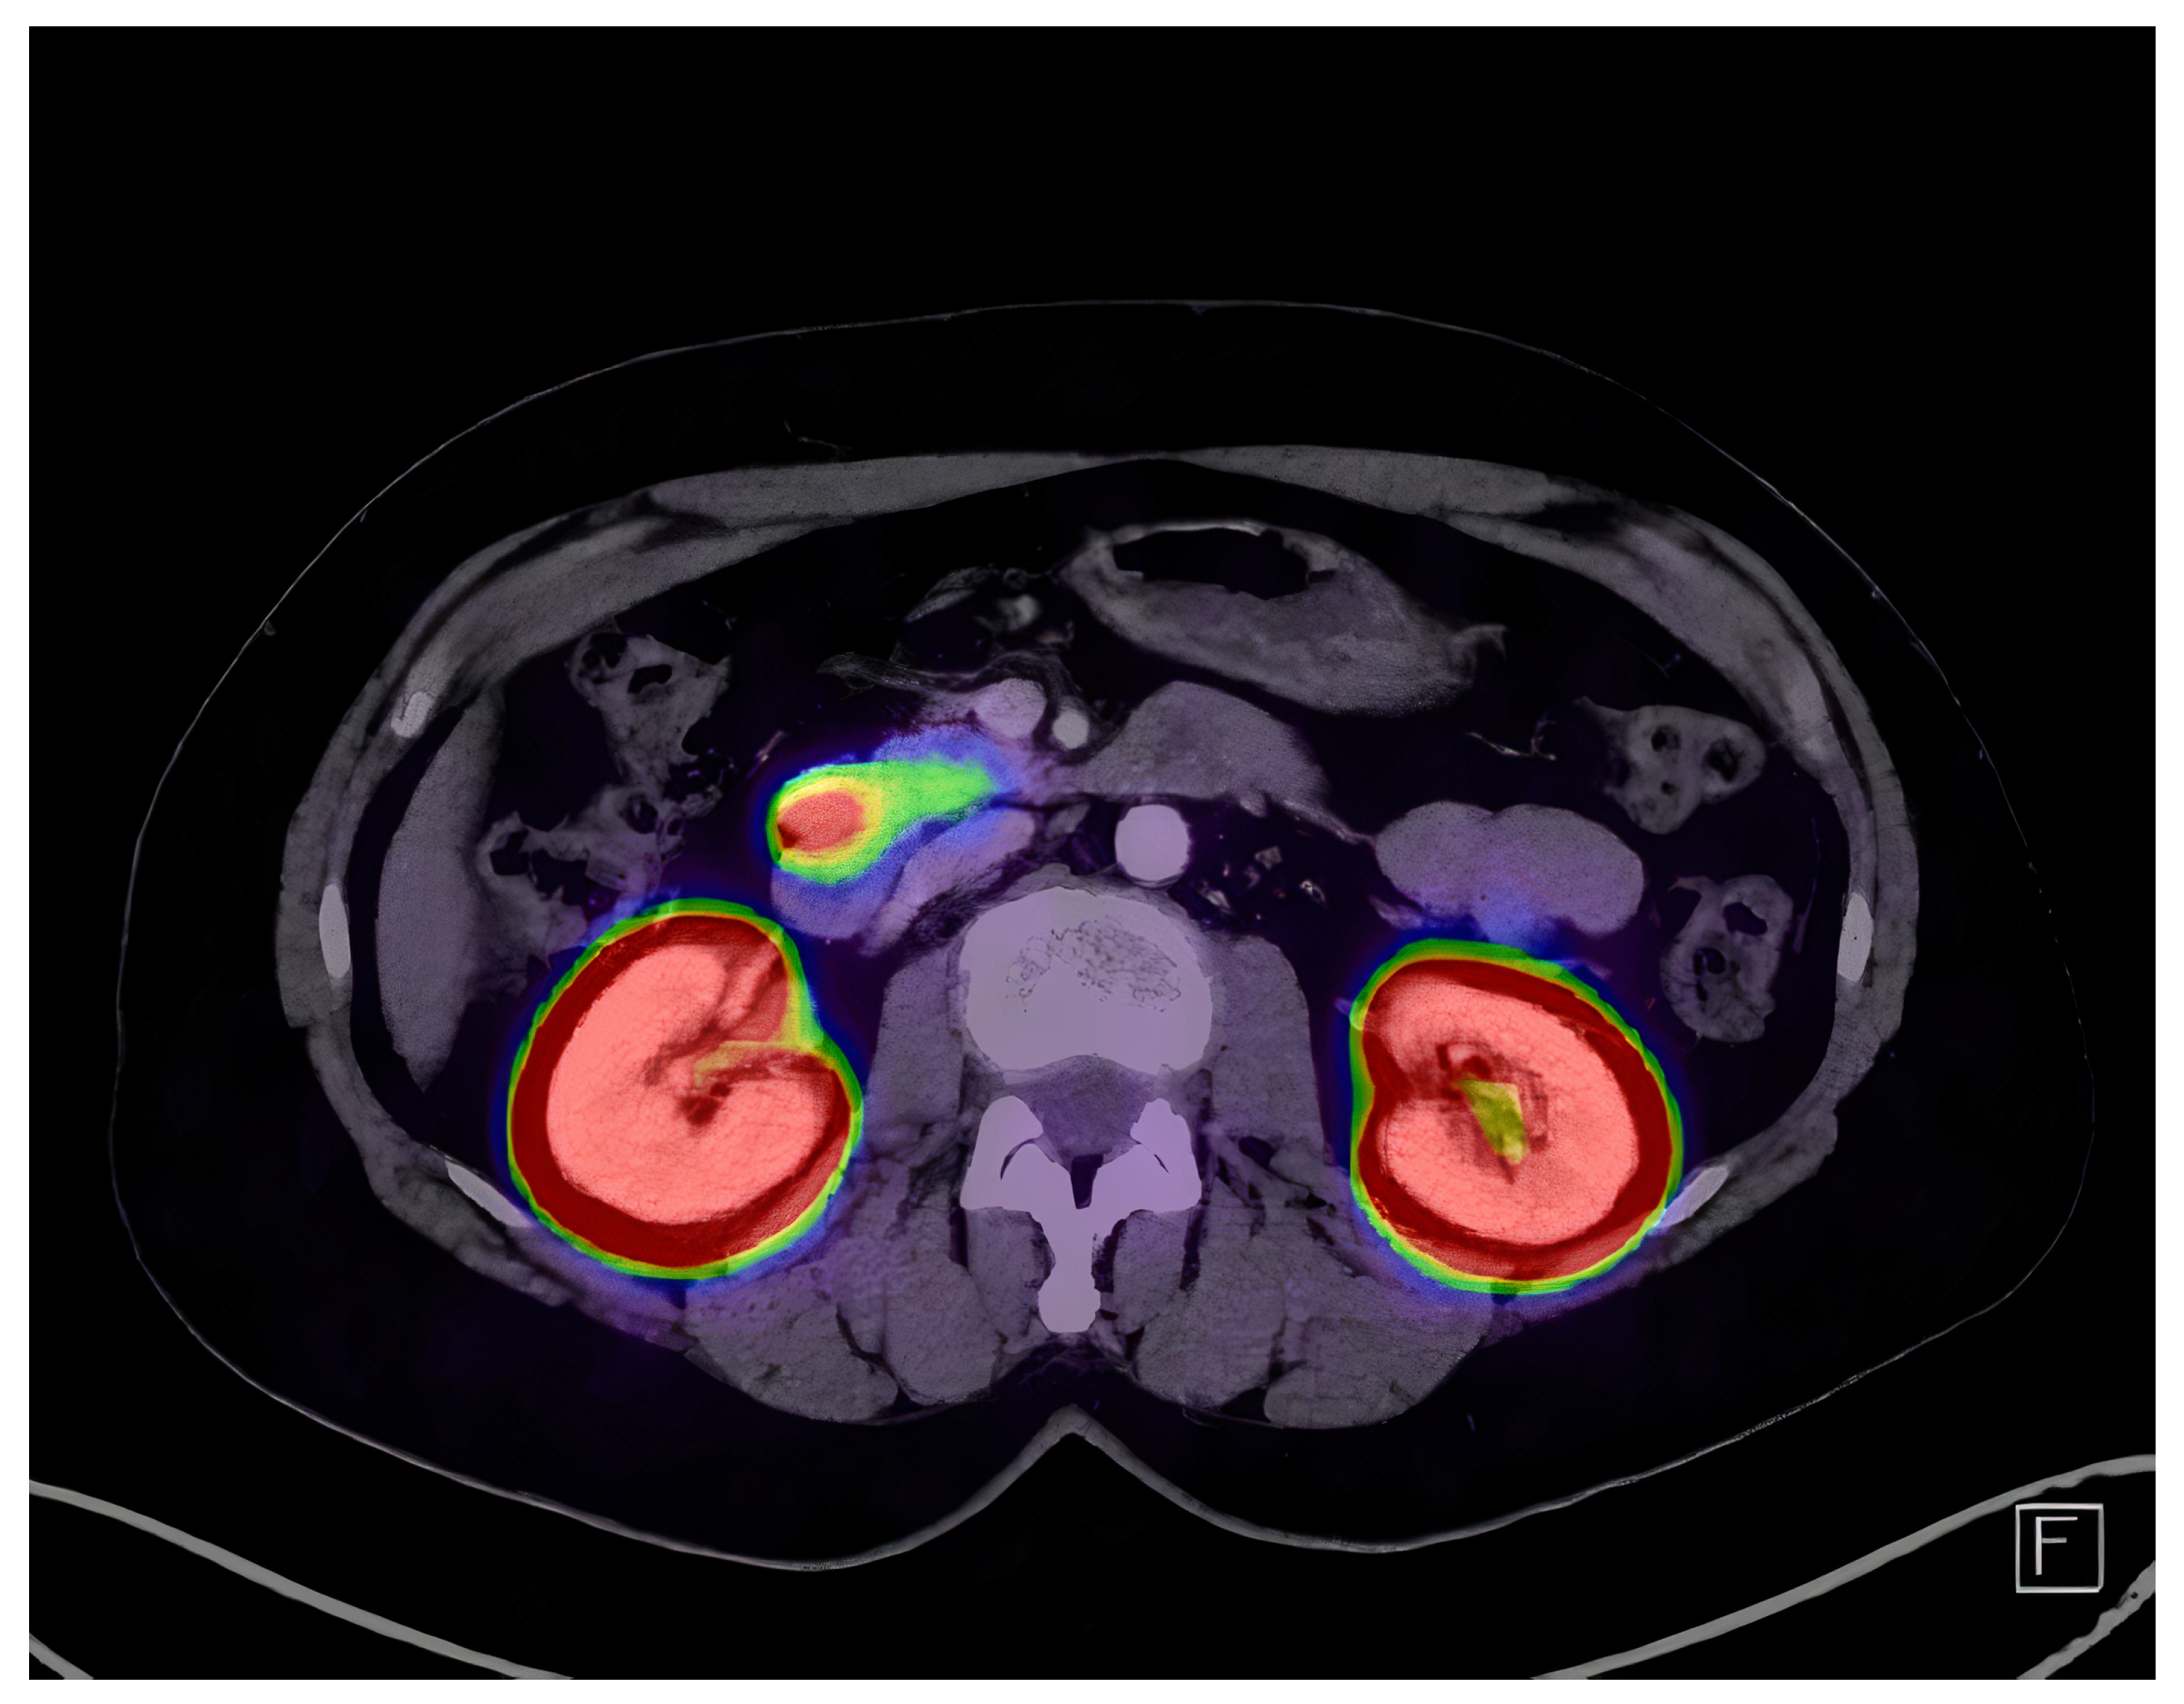

2.3. Imaging and Localization

| Exendin-4 PET/CT | 94% (85–98%) | [25,31,32,33,35] |